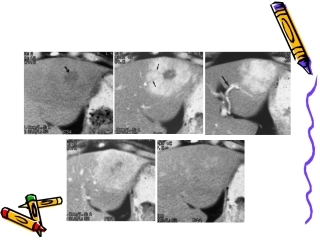

1平扫动脉期门脉期延迟10’2局灶性结节性增生局灶性结节性增生((FNHFNH)的影像学诊断与)的影像学诊断与鉴别诊断鉴别诊断FNHFocalnodula...

FNH影像学诊断及鉴别诊断2013级影像科林倩Focalnodularhyperplasia良性肿瘤样病变,近年不少见由肝细胞、血管、小胆管、Kupffer细胞等...

FNH影像学诊断及鉴别诊断FNH概述良性肿瘤样病变,由肝细胞、血管、小胆管、Kupffer细胞等构成,病灶中央含有较多的纤维基质,并常形成星形...